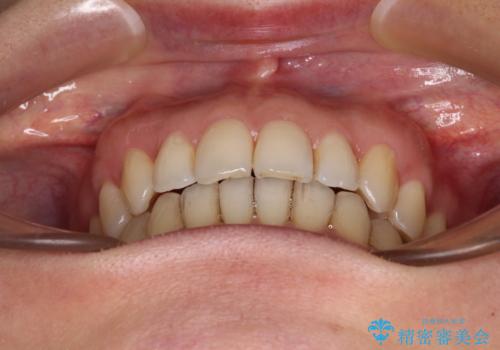

矯正治療の後戻り インビザライン・ライトによる矯正治療

- 矯正治療の後戻りを気にして来院された患者様です。

後戻りは軽微であったので、インビザライン・ライトにより矯正治療を行うこととしました。

インビザライン・ライトは提供されるマウスピースの数に制限があり、通常のタイプよりもマウスピース提供期間が短くなっている一方、安価に治療を行うことができるプランです。

治療のゴールも変更できないため、軽微な歯列不正や、後戻り改善などに適しています。